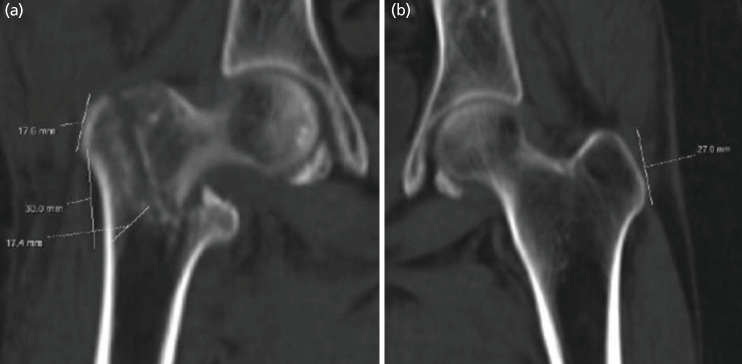

Introduction: The Intertrochanteric fracture is a common hip trauma encountered in elderly patients. There is a lack of general agreement regarding its surgical management and choice of implant. Purpose of this study to conclude the final decision matrix regarding surgical management of intertrochanteric fractures based on parameters assessed on plain radiographs and CT scan.

Materials and methods: We have retrospectively evaluated 55 patients with intertrochanteric fractures presented to our institute after informed consent with radiographs and CT scans between July 2017 to July 2018. Assessment of various parameters regarding fracture geometry and classification as well as measurement was done.

Results: Mean lateral wall thickness in present study was 20.76mm. Incidence of coronal fragments was 90.9% and absence of coronal fragment in 5 patients. We noted the cases with anterior comminution had also a posterior comminution rendered the fracture unstable in almost 20 % cases.

Conclusion: Better understanding of fracture geometry by combined used of radiograph and CT scan enhanced preoperative planning, choice of suitable implant, helps in reduction manoeuvre and improving quality of osteosynthesis.